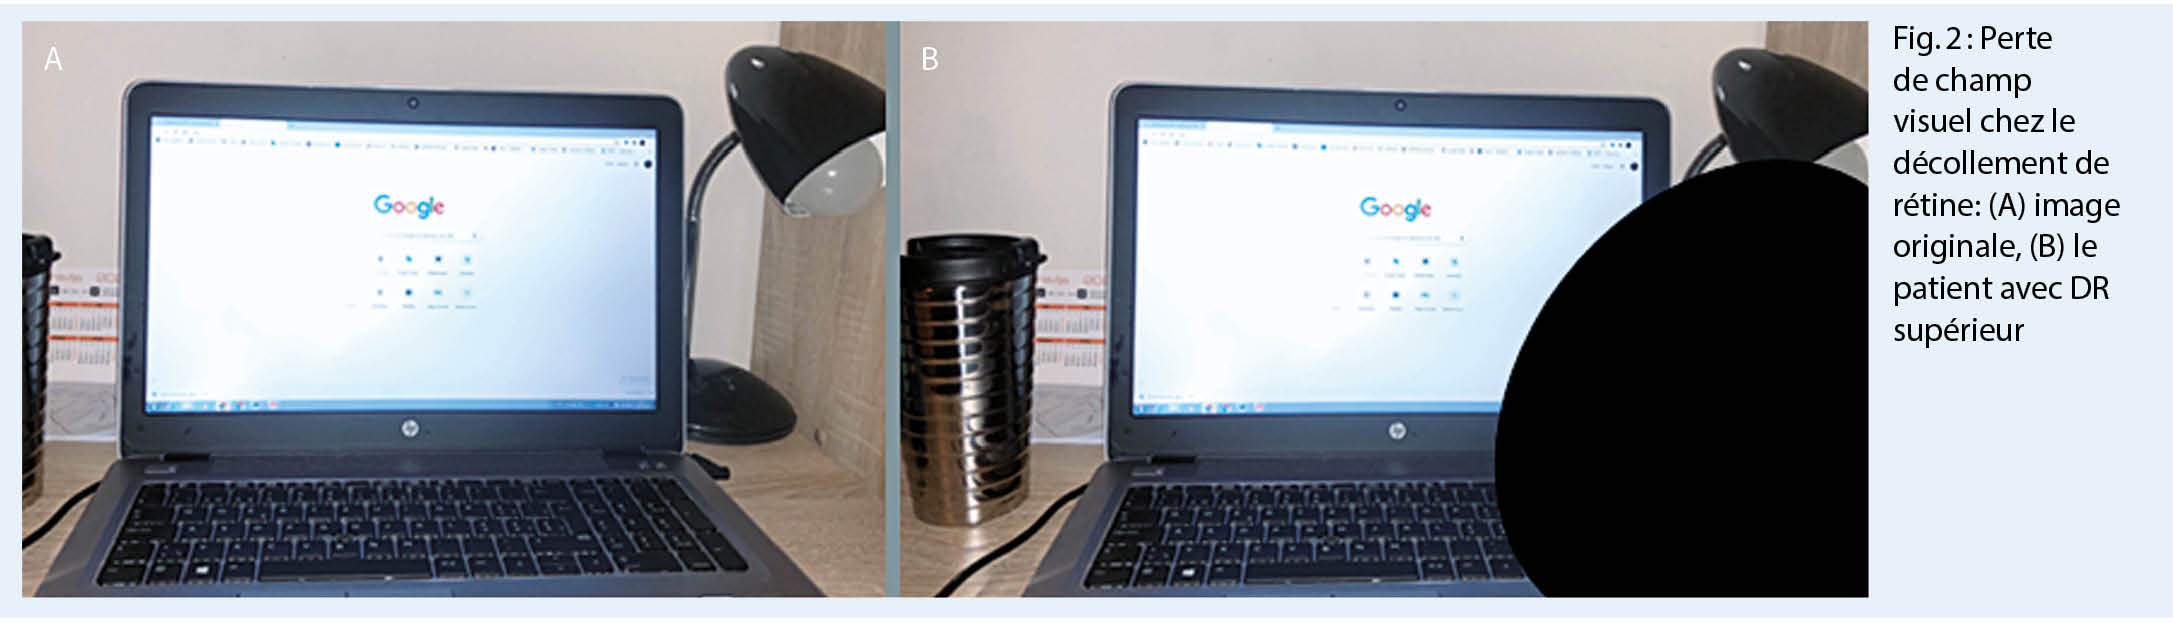

2. présence d’ une voile ou rideau dans une partie du champ visuel qui s’ élargit progressivement (fig. 2)

Le diagnostic du DR est basé sur l’ examen ophtalmologique avec les pupilles dilatées et sur une bonne anamnèse (1-4), i.e. la position du voile dans le champ visuel correspond à la partie de la rétine surélevée, qui est « inversée » dans l’ œil (la figure 2b montre le voile en inférieur qui correspond à un DR supérieur). L’ examen standard comprend : l’ acuité visuelle, la pression intraoculaire, l’ examen de la partie antérieure de l’ œil à la lampe à fente et ensuite l’ examen du vitré et du fond d’ œil avec les pupilles dilatées. Dans le vitré, on peut observer de la « poussière de tabac », c’ est-à-dire de petites parties de l’ épithélium pigmentaire rétinien déchirées (1, 3). Le diagnostic définitif est posé par ophtalmoscopie indirecte, lorsque la rétine décollée avec une ou plusieurs déchirures peut être observée (fig. 3A). Dans le cas où la déchirure de la rétine a aussi déchiré un vaisseau sanguin de la rétine, il y a une hémorragie vitréenne, qui empêche l’ophtalmoscopie indirecte. Dans ce cas, le diagnostic définitif est posé par l’ échographie (fig. 3B). Dans les plus grands hôpitaux, bien équipés, une imagerie de la rétine est faite aussi en supplément (OCT = la tomographie en cohérence optique), qui donne des informations microscopiques précises des changements dans les couches rétiniennes (fig. 3C) (1, 3). Ces informations peuvent aider pour estimer la récupération fonctionnelle.